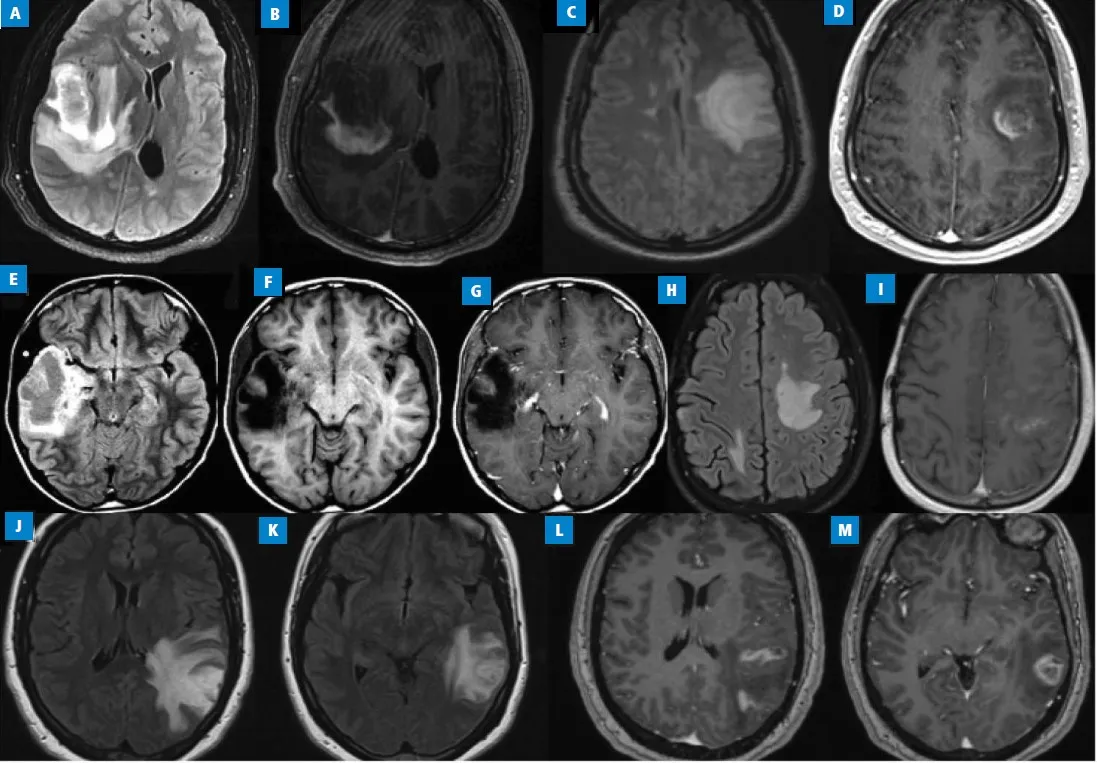

W przypadku podejrzenia guza mózgu, kluczowe są badania obrazowe, które pozwalają na dokładną ocenę stanu mózgu. Najczęściej stosowanymi metodami są rezonans magnetyczny (MRI) oraz tomografia komputerowa (CT). MRI jest szczególnie skuteczne w identyfikacji zmian w tkankach mózgowych, a także w ocenie ich lokalizacji i rozmiaru. Z kolei CT jest często stosowane w sytuacjach nagłych, gdy potrzebna jest szybka diagnoza. Te badania pozwalają lekarzom na postawienie diagnozy oraz zaplanowanie dalszych działań terapeutycznych.

| Rezonans magnetyczny (MRI) | Badanie obrazowe, które wykorzystuje pole magnetyczne do tworzenia szczegółowych obrazów mózgu. |